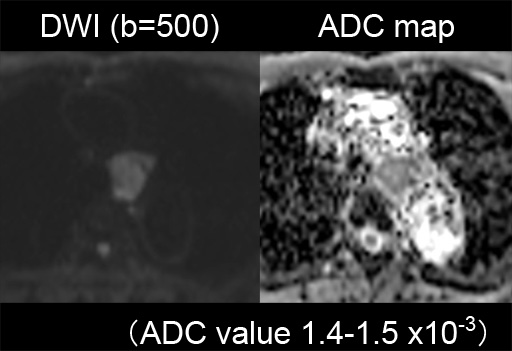

(dynamic study) 図12 DWI (b=500), ADC map

図12 DWI (b=500), ADC map